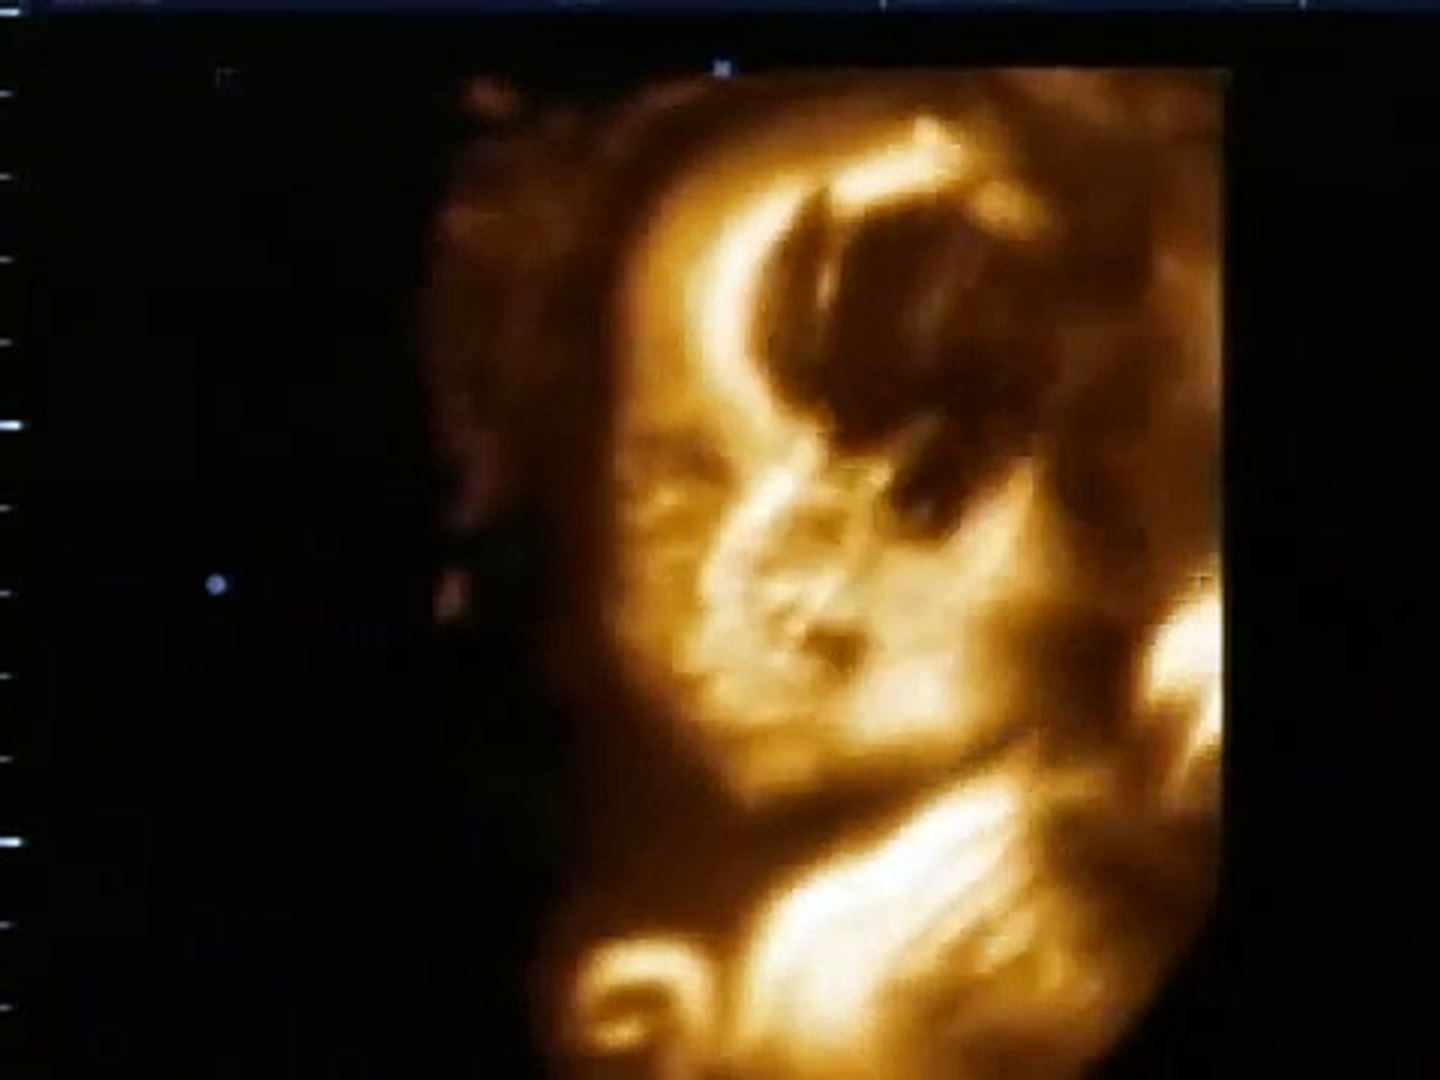

25 Week Ultrasound Girl 3d

The girl ultrasound gallery is designed to show you what a baby girl looks like on ultrasound photos from various weeks of pregnancy. 3d ultrasound 25 weeks 4d view of baby 25 week pregnancy baby girl first view. A new conception 3d 4d ultrasound studio 1193832 views. Our labor and delivery vlog 38 weeks baby girl is finally here.

However we do recommend a gestational age of 26 34 weeks for the best facial detail. 25 weeks pregnancy ultrasound. 3d 5d ultrasound images and 4d ultrasound video can be obtained at any stage. Perhaps the doctor will refer you for an ultrasound.

Each week in pregnancy can look slightly different. Im scheduled to have one tomorrow and the tech said the best results are at 28 weeks and i just cant wait that long since my husband is likely to deploy and i want to do this before. She said usually during 20s weeks is when they are a lot easier to do just because baby looks like a baby and they still have some room in there to get good enough pictures. Clair shores michigan 95 posts aug 6th 10 anyone get a 3d ultrasound at 25 weeks.

3d ultrasound at 25 weeks ashleekozlinski 1 child.